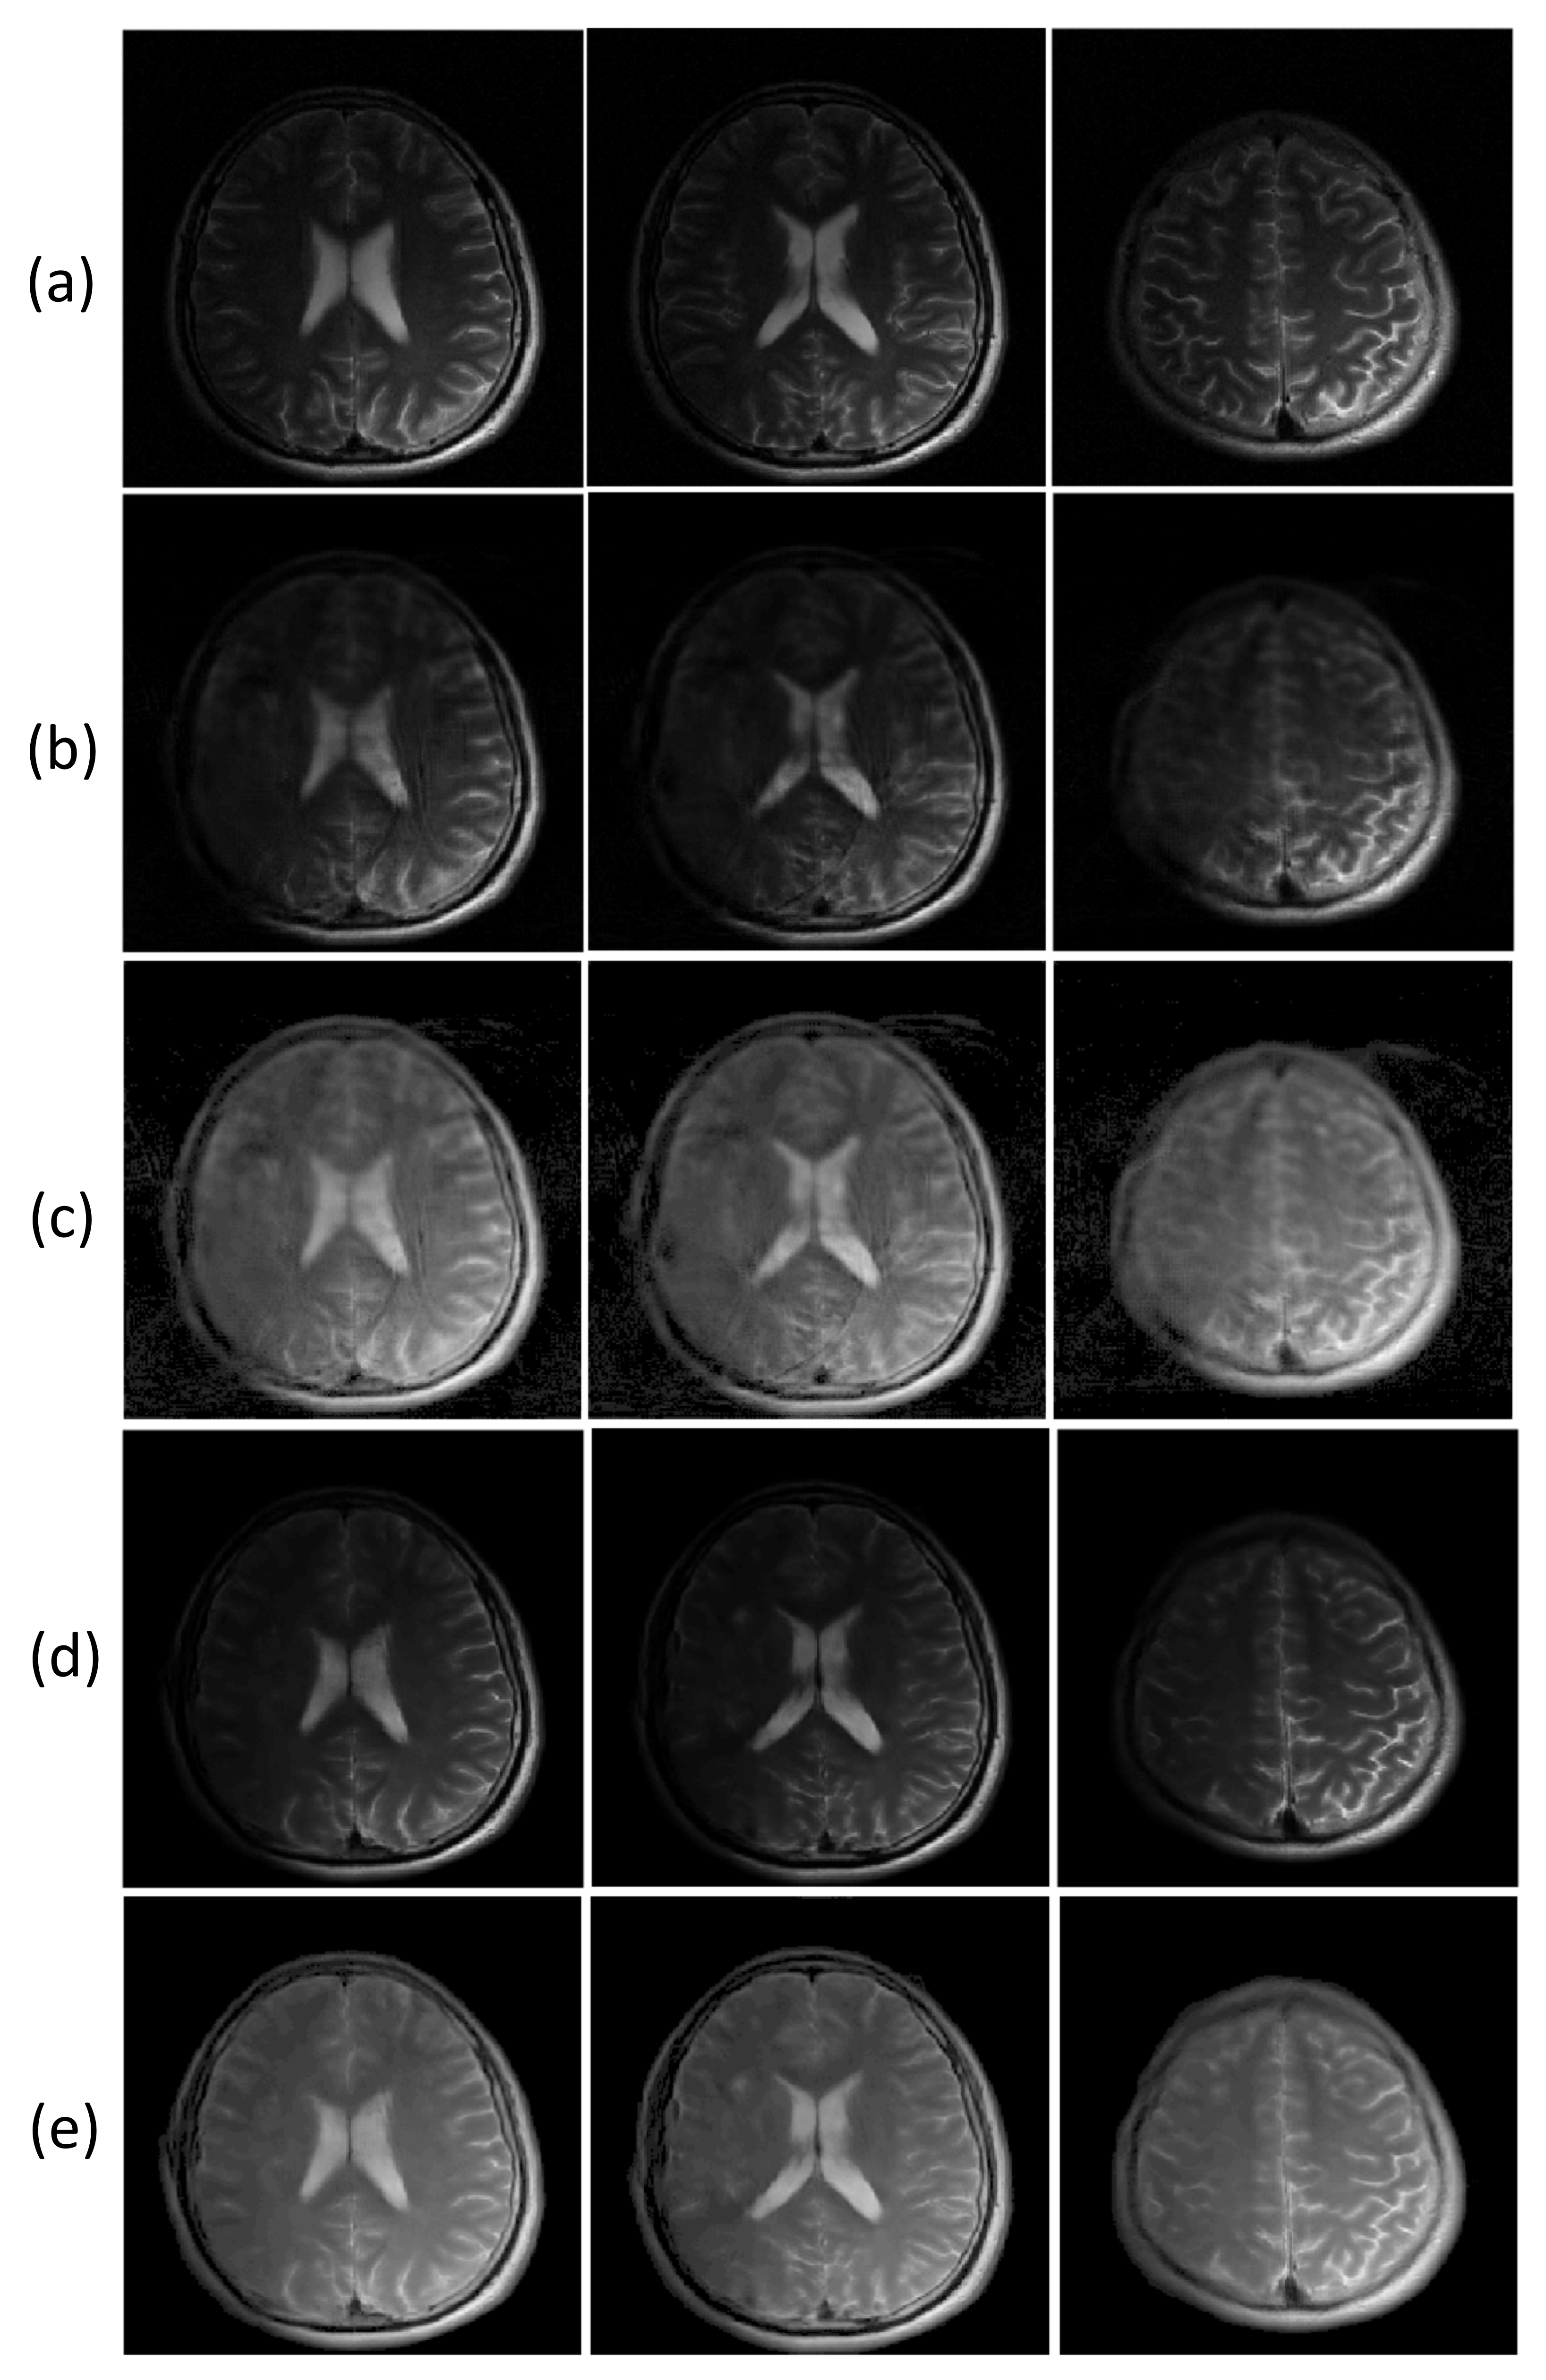

The reconstructed images from radially sampled k-space data are shown in Figure 9. When the filtered back projection was used to reconstruct the images from the undersampled radial k-space data, the streaking artifacts could be observed in the images, as shown in Figure 9 (rows 2). In contrast, the ETER-net provided improved image quality (rows 3 and 4). Moreover, the comparison of the images in rows 3 and 4 demonstrates that the loss function including Euclidean distance, adversarial loss, and perceptual loss improved the image quality. The improvement owing to the additional loss functions can also be validated by the quantitative measures in Table 1. The average nMSE is 3.51% for the filtered back projection, 1.98% for the proposed method with L1 loss only, and 1.49% for the proposed method with additional losses. In terms of SSIM, the average score of the filtered back projection is 0.786, the average score of the proposed method with L1 loss only is 0.922, and the average score of the proposed method with additional losses is 0.938. The proposed method with additional losses shows the least error and highest SSIM.

Figure 9.

Comparison of inverse Radon transform with the proposed method with/without additional losses. Four example images reconstructed from radial k-space data with 100 view angles are shown. Label: reconstructed images from radial k-space data with 400 view angles by inverse Radon transform, Radon: inverse Radon transform, Base: the proposed method with the baseline loss function, GAN + VGG: the proposed method with additional adversarial and perceptual losses.